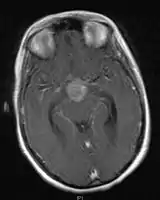

- Mainly located in midline structures, suprasellar region or pineal gland, also basal ganglia and hypothalamus

- Pineal Gland Germinoma

- Suprasellar Germinoma

- Whole ventricular volume: 3rd, 4th, lateral, prepontine cistern

- Involved field volume: pre-chemotherapy volume + clinical margin 1-1.5 cm